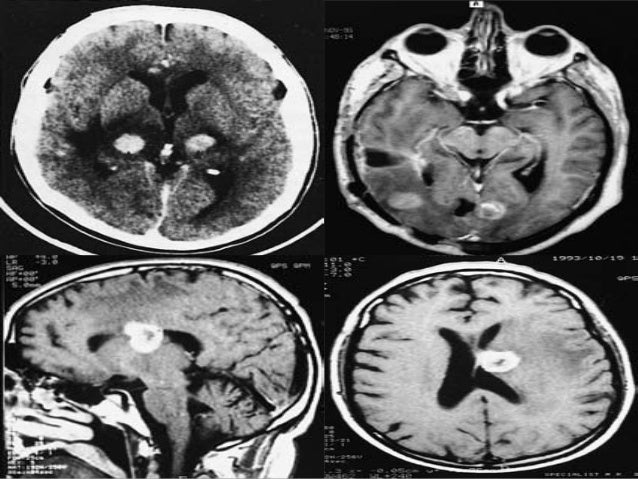

It is used to diagnose tumors, infection, inflammation, and other brain disorders. A biopsy means taking a small tissue sample from your brain and examining it under the microscope. A brain tumor is an abnormal growth of tissue in the brain or central spine that can disrupt proper a biopsy may be necessary, so a pathologist can be brought in to help identify the brain tumor type.

Specimens are taken from normal tissue, edema, solid tumor and central necrosis.

A stereotactic biopsy is a surgical procedure where a thin needle is inserted into the brain by a neurosurgeon to extract a small piece of tissue to examine. A biopsy is a major procedure, and it is the most definitive test for brain tumor diagnosis. A brain biopsy can help doctors diagnose brain illnesses, allowing them to devise treatment plans. These are generally seen in stereotactic biopsy: